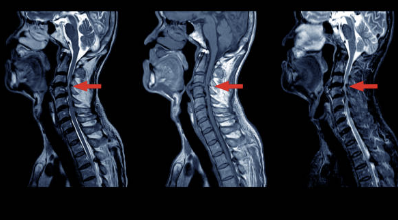

목 디스크는 경추 부위에서 발생하는 디스크 이상 중 하나입니다. 디스크는 척추 각 뼈 사이에 위치한 연골 조직으로, 척추를 보호하고 충격을 완화하는 역할을 합니다. 디스크는 외부 경계를 둘러싼 섬유성 껍질과 내부를 채우는 젤 형태의 핵으로 구성되어 있습니다. 목 디스크가 이상을 보면, 핵이 껍질을 뚫고 나와 인접한 신경을 압박하게 되어 목의 통증, 근경련, 무력감, 저림 현상 등의 증상을 유발할 수 있습니다. 목 디스크는 일상생활에서의 부상이나 과도한 스트레스 등에 의해 발생할 수 있으며, 적절한 치료 없이 방치하면 심한 증상을 유발할 수 있습니다.

목 디스크는 경추 부위의 디스크 이상 중 하나로, 인접한 신경을 압박하여 다양한 증상을 유발할 수 있습니다. 다음은 목 디스크의 주요 증상 5가지에 대한 상세한 설명입니다.

- 저림 현상: 목 디스크로 인해 인접한 신경이 압박되면, 손가락이나 팔, 어깨 등에서 저림 현상이 나타날 수 있습니다. 이러한 증상은 다양한 정도로 나타날 수 있으며, 가끔은 동통과 함께 나타날 수도 있습니다.

- 무력감: 목 디스크로 인해 신경이 압박되면, 근육을 움직이는 데 필요한 신경 신호가 올바르게 전달되지 않아 근력이 감소될 수 있습니다. 이러한 무력감은 손, 팔, 어깨 등 다양한 부위에서 나타날 수 있습니다.